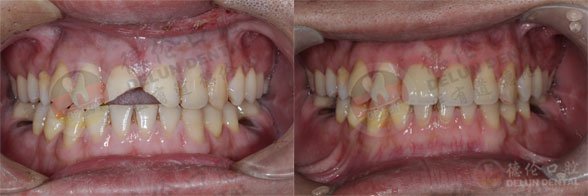

美容冠修复前后对比图片

查看更多德伦口腔美容冠修复案例>>>